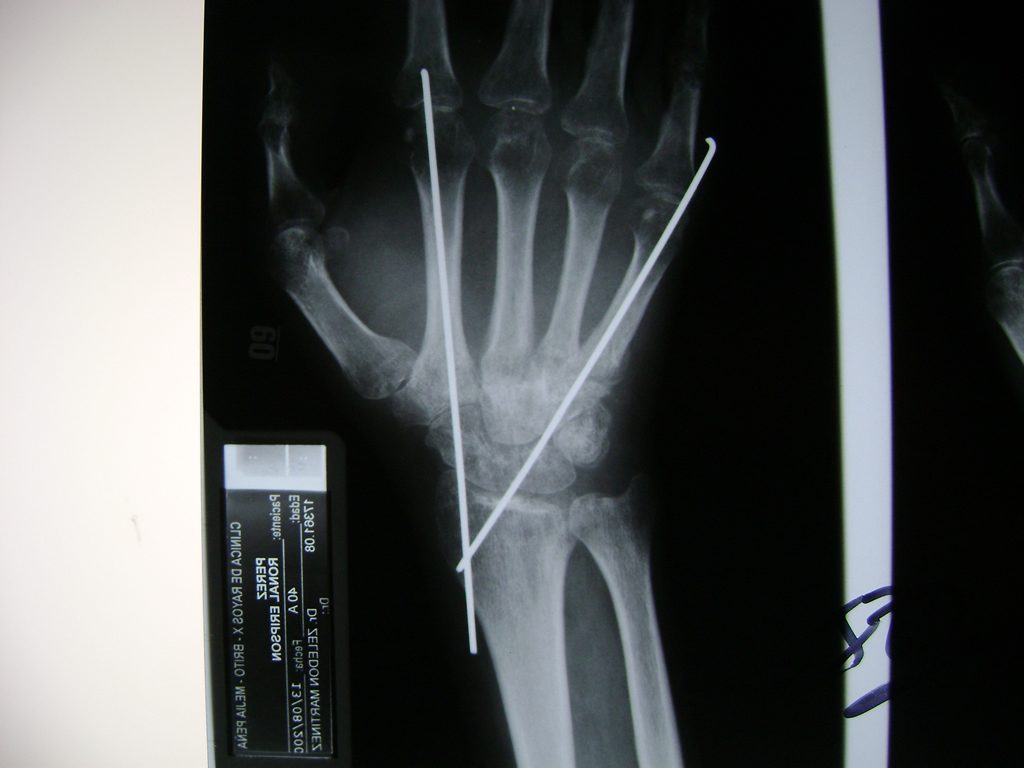

Cirugías de Calcaneo - Cirugías de Muñecas y Manos

Los procedimientos más comunes en cirugía de la mano son aquellos destinados a reparar traumatismos, incluyendo lesiones de tendones, nervios, vasos sanguíneos, y articulaciones; huesos fracturados; y quemaduras, cortes, y otros daños de la piel.